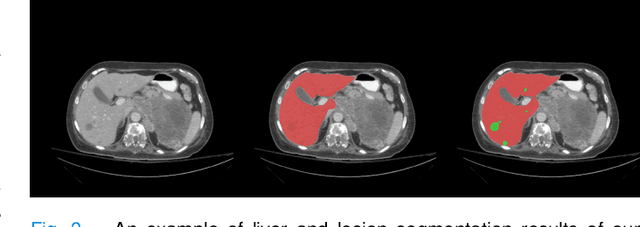

Abstract:Accurate liver and lesion segmentation from computed tomography (CT) images are highly demanded in clinical practice for assisting the diagnosis and assessment of hepatic tumor disease. However, automatic liver and lesion segmentation from contrast-enhanced CT volumes is extremely challenging due to the diversity in contrast, resolution, and quality of images. Previous methods based on UNet for 2D slice-by-slice or 3D volume-by-volume segmentation either lack sufficient spatial contexts or suffer from high GPU computational cost, which limits the performance. To tackle these issues, we propose a novel context-aware PolyUNet for accurate liver and lesion segmentation. It jointly explores structural diversity and consecutive t-adjacent slices to enrich feature expressive power and spatial contextual information while avoiding the overload of GPU memory consumption. In addition, we utilize zoom out/in and two-stage refinement strategy to exclude the irrelevant contexts and focus on the specific region for the fine-grained segmentation. Our method achieved very competitive performance at the MICCAI 2017 Liver Tumor Segmentation (LiTS) Challenge among all tasks with a single model and ranked the $3^{rd}$, $12^{th}$, $2^{nd}$, and $5^{th}$ places in the liver segmentation, lesion segmentation, lesion detection, and tumor burden estimation, respectively.